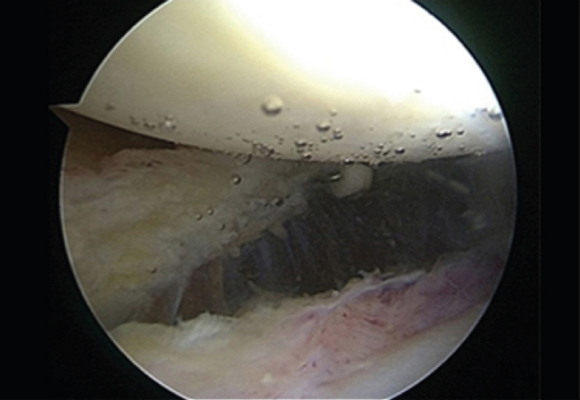

노화된 어깨의 관절낭을 절제해 간격을 넓혀주는 수술 시행

ㆍ환자의 동의를 받은 자료이며, 이미지 사진은 실물과 다를 수 있습니다. (16.09.30)